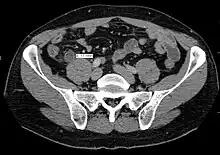

A CT scan demonstrating acute appendicitis (note the appendix has a diameter of 17.1 mm and there is surrounding fat stranding)

A fecalith marked by the arrow that has resulted in acute appendicitis.

Where it is readily available, computed tomography (CT) has become frequently used, especially in people whose diagnosis is not obvious on history and physical examination. Although some concerns about interpretation are identified, a 2019 Cochrane review found that sensitivity and specificity of CT for the diagnosis of acute appendicitis in adults was high.[59] Concerns about radiation tend to limit use of CT in pregnant women and children, especially with the increasingly widespread usage of MRI.[60][61]

The accurate diagnosis of appendicitis is multi-tiered, with the size of the appendix having the strongest positive predictive value, while indirect features can either increase or decrease sensitivity and specificity. A size of over 6 mm is both 95% sensitive and specific for appendicitis.[62]

However, because the appendix can be filled with fecal material, causing intraluminal distention, this criterion has shown limited utility in more recent meta-analyses.[63] This is as opposed to ultrasound, in which the wall of the appendix can be more easily distinguished from intraluminal feces. In such scenarios, ancillary features such as increased wall enhancement as compared to adjacent bowel and inflammation of the surrounding fat, or fat stranding, can be supportive of the diagnosis. However, their absence does not preclude it. In severe cases with perforation, an adjacent phlegmon or abscess can be seen. Dense fluid layering in the pelvis can also result, related to either pus or enteric spillage. When patients are thin or younger, the relative absence of fat can make the appendix and surrounding fat stranding difficult to see.[63]